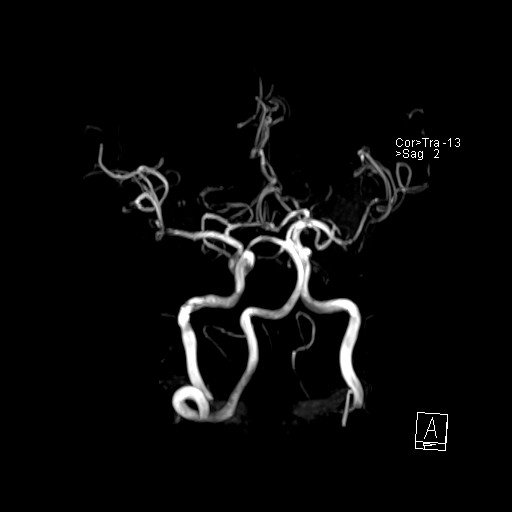

239716 - VILLANUEVA, WILLIAM A. - Number 4 |

|

239716 - VILLANUEVA, WILLIAM A. - Number 4 |